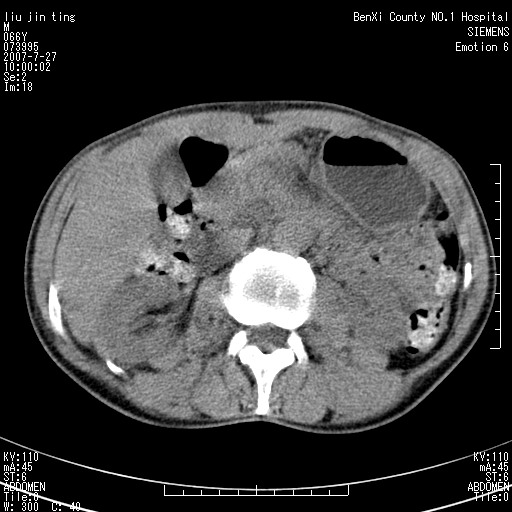

腹痛,背痛,无恶心呕吐,不黄,彩超示胰腺钩癌,ct扫描病灶平扫30-40hu,增强后动脉期40--60hu,静脉期50-68hu,真的是钩突上的么?您要试一试么?

动脉期

静脉期